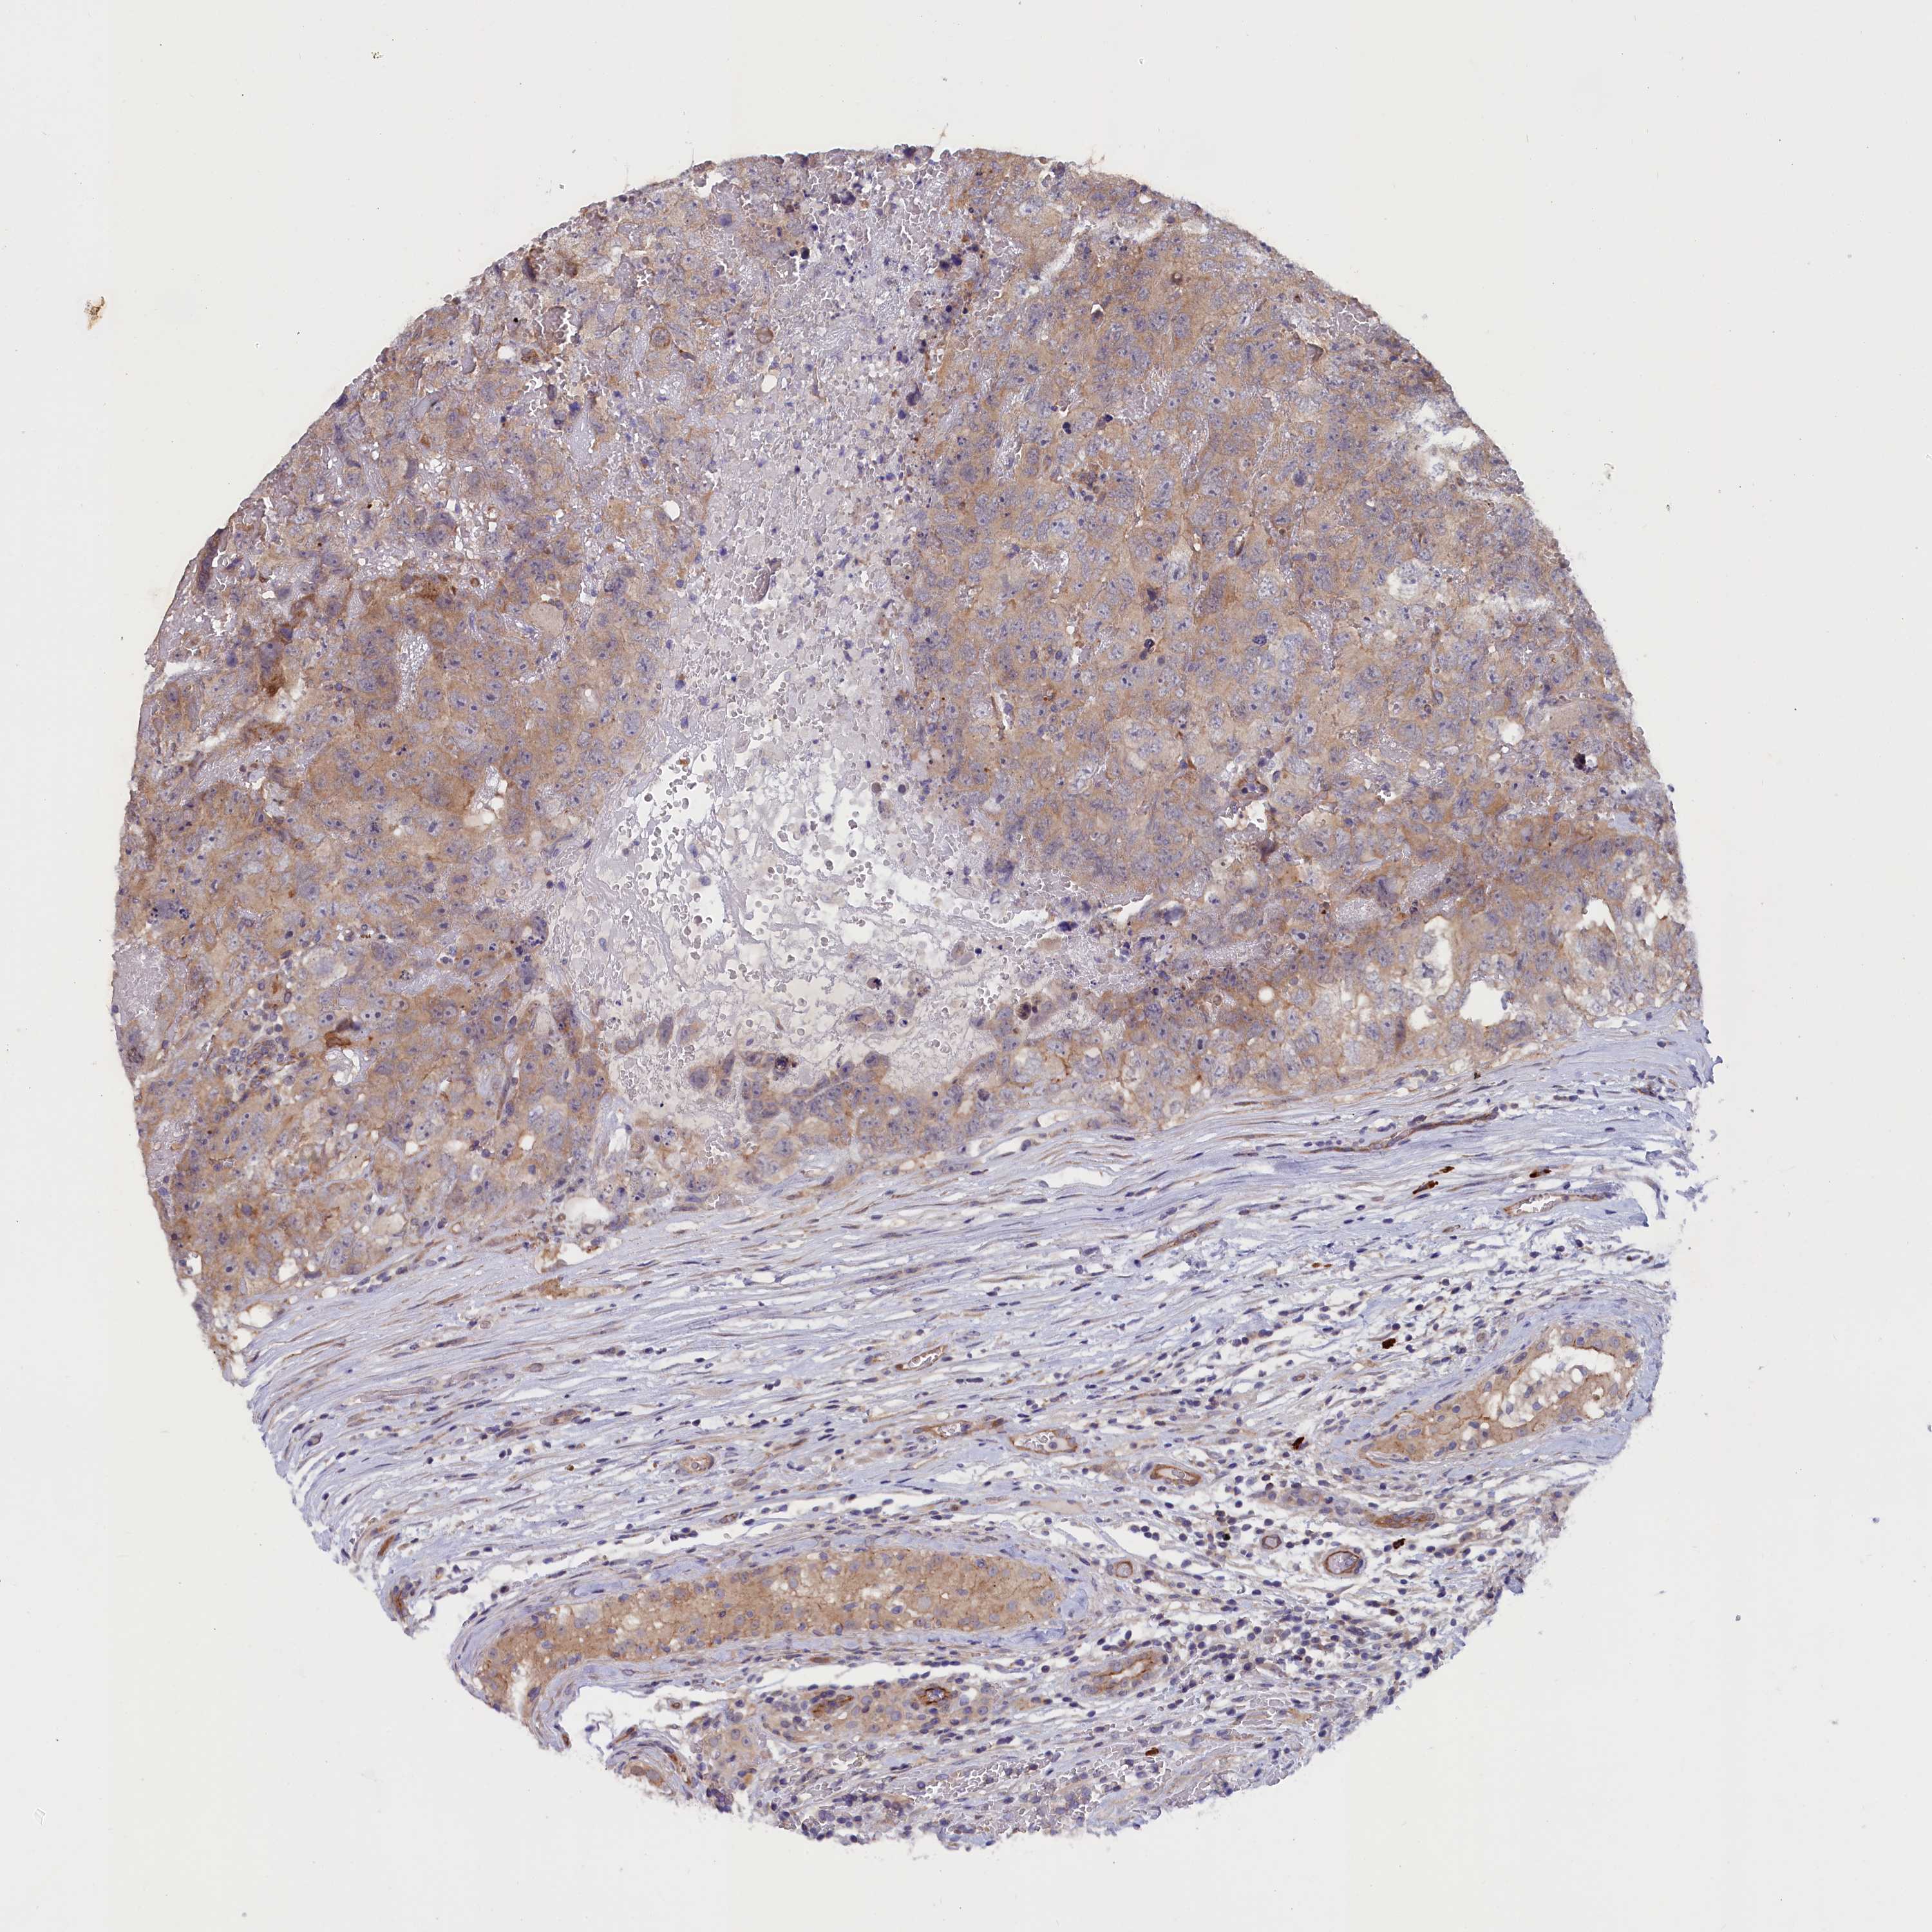

TESTIS CANCER - Protein expressioni

A mouse-over function shows sample information and annotation data. Click on an image to view it in a full screen mode. Samples can be filtered based on level of antibody staining by selecting one or several of the following categories: high, medium, low and not detected. The assay and annotation is described here.

Note that samples used for immunohistochemistry by the Human Protein Atlas do not correspond to samples in the TCGA dataset.

Antibody stainingi

Antibody staining in the annotated cell types in the current human tissue is reported as not detected, low, medium, or high, based on conventional immunohistochemistry profiling in selected tissues. This score is based on the combination of the staining intensity and fraction of stained cells.

Each image is clickable and will lead to virtual microscopy that enables deeper exploration of all samples and also displays staining intensity scores, fraction scores and subcellular localization as well as patient and tissue information for each sample.

Antibody HPA041888

Antibody HPA041908

Staining

High

Medium

Low

Not detected

Intensity

Strong

Moderate

Weak

Negative

Quantity

>75%

75%-25%

<25%

None

Location

Nuclear

Cytoplasmic/membranous

Cytoplasmic/membranous,nuclear

Carcinoma, Embryonal, NOS

Seminoma, NOS

Urothelial carcinoma, High grade